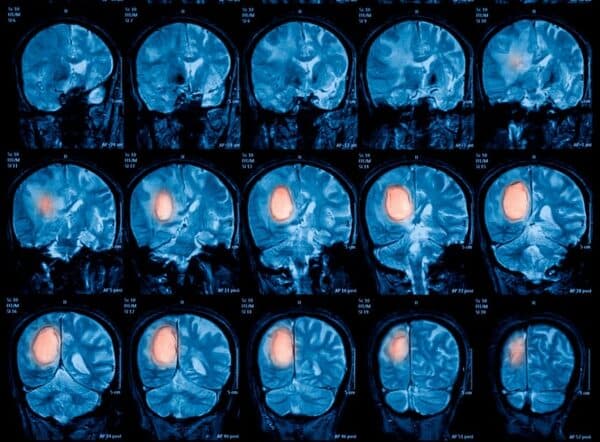

Profesionales, del Departamento de Neurocirugía de la Facultad de Ciencias Médicas de la UNA, realizaron una importante cirugía para extirpar un tumor cerebral en una paciente que se mantuvo despierta durante la intervención.

En día muy importante para la medicina local, por primera vez los especialistas de la Facultad de Ciencias Médicas extirparon un tumor cerebral a una paciente con gliomas, utilizando una innovadora técnica denominada “Awake” o craneotomía en paciente despierto.

La Dra. Neurocirujana Gabriela Moguilner, explicó a la 1080 AM que este tipo de cirugías se realiza cuando aparecen gliomas (tumores primarios del sistema nervioso central que se ubican en el cerebro). Cuando los mismos afectan a las funciones como el habla o el movimiento, es cuando se precisa una intervención con el paciente despierto.